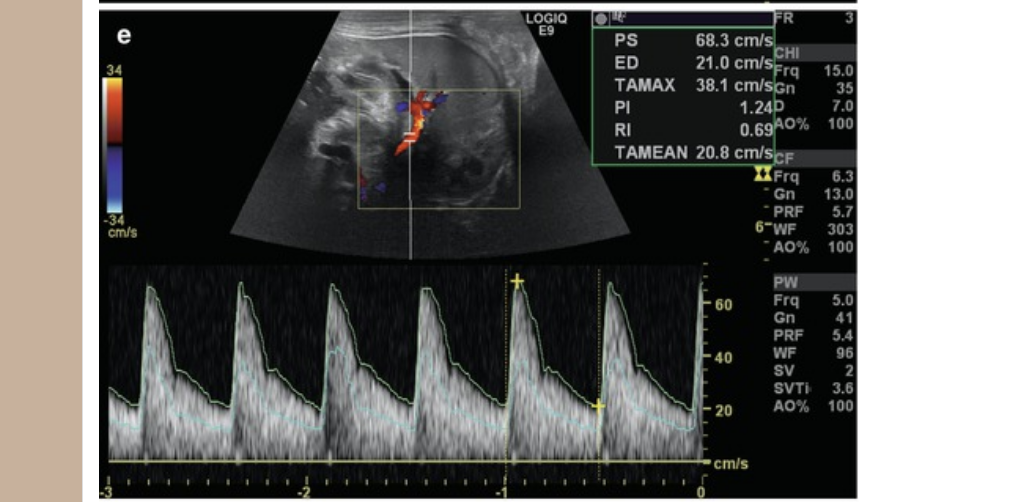

![<p>which describes a normal renal artery waveform</p><p>.</p><p>a) low resistance w/increased diastolic flow</p><p>b) increased diastolic flow reversal</p><p>c) biphasic w/mild diastolic flow reversal</p><p>d) pulsus alternans [methodical variation in peak vel on every other beat]</p>](https://knowt-user-attachments.s3.amazonaws.com/8c8e8b11-eaa0-4474-8147-a50abca9736d.png)

which describes a normal renal artery waveform

.

a) low resistance w/increased diastolic flow

b) increased diastolic flow reversal

c) biphasic w/mild diastolic flow reversal

d) pulsus alternans [methodical variation in peak vel on every other beat]

a. low resistance w/increased diastolic flow